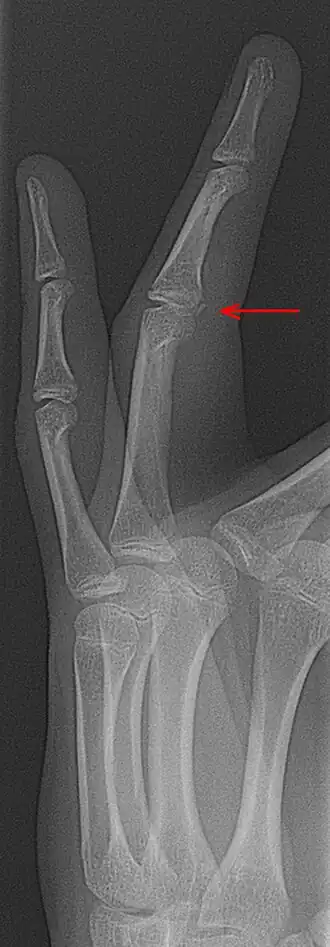

Een avulsiefractuur[1] is een fractuur ontstaan door grote trekkracht van een pees aan het bot. Doordat de pees meer trekkracht kan verdragen, zal eerder een stuk bot afscheuren dan de pees.